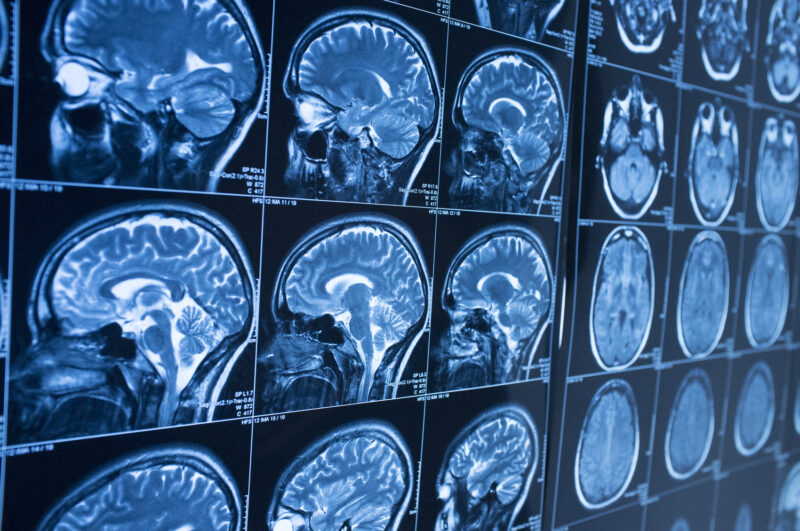

A concussion is a form of traumatic brain injury that can occur after a bump, blow, or jolt to the head. While many people expect symptoms to appear right away, some concussion effects develop hours or even days later.

These delayed concussion symptoms can be subtle at first but may worsen over time. In this article, we break down common head injury delayed symptoms one by one so you know exactly what to watch for after a head injury.